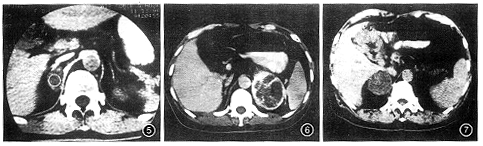

图1~3 右肾上腺无功能腺瘤。图1为CT平扫,肿瘤CT值38 HU。图2为CT增强扫描,肿瘤CT值增至44 HU。图3为CT像素矩阵图分析,瘤内有轻度负CT值区域

图5 右肾上腺无功能腺瘤。CT平扫,肿瘤与正常肾上腺相连,CT值-8 HU 图6 肺癌左肾上腺转移瘤。CT增强扫描,肿瘤呈不规则厚环状强化 图7 胃癌患者,右肾上腺肿块。CT平扫,肿瘤密度欠均匀,CT值29 HU

图8 与图7同一病例,CT增强扫描,肿瘤呈不均匀强化,CT值55 HU,手术证实为肾上腺腺瘤

各种CT征象对肾上腺腺瘤与转移瘤鉴别诊断的价值见附表。肿瘤与相对正常的肾上腺相连、平扫CT值<0 HU或CT像素矩阵图上有轻度负CT值区域只见于腺瘤;肿瘤边界模糊或(和)侵犯周围结构、呈不规则厚环状强化则是转移瘤的特异性指标(图5,6)。本组符合一项特异性指标或四项非特异性指标以上者的总体符合率是93% (101/109),3例无功能腺瘤和2例Cushing综合征腺瘤难与恶性肿瘤区分(图7,8),3例转移瘤误为良性腺瘤。